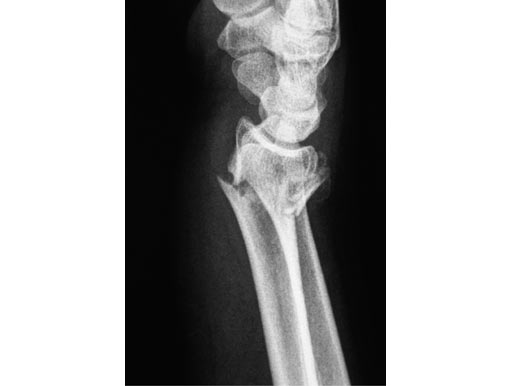

56-year-old female, accident at home